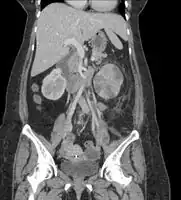

If a kidney stone is suspected (e.g. on the basis of characteristic colicky pain or the presence of a disproportionate amount of blood in the urine), a kidneys, ureters, and bladder x-ray (KUB film) may assist in identifying radioopaque stones.[9] Where available, a noncontrast helical CT scan with 5 millimeter sections is the diagnostic modality of choice in the radiographic evaluation of suspected nephrolithiasis.[17][18][19] All stones are detectable on CT scans except very rare stones composed of certain drug residues in the urine.[20] In patients with recurrent ascending urinary tract infections, it may be necessary to exclude an anatomical abnormality, such as vesicoureteral reflux or polycystic kidney disease. Investigations used in this setting include kidney ultrasonography or voiding cystourethrography.[9] CT scan or kidney ultrasonography is useful in the diagnosis of xanthogranulomatous pyelonephritis; serial imaging may be useful for differentiating this condition from kidney cancer.[10]

Xanthogranulomatous pyelonephritis is an unusual form of chronic pyelonephritis characterized by granulomatous abscess formation, severe kidney destruction, and a clinical picture that may resemble renal cell carcinoma and other inflammatory kidney parenchymal diseases. Most affected individuals present with recurrent fevers and urosepsis, anemia, and a painful kidney mass. Other common manifestations include kidney stones and loss of function of the affected kidney. Bacterial cultures of kidney tissue are almost always positive.[25] Microscopically, there are granulomas and lipid-laden macrophages (hence the term xantho-, which means yellow in ancient Greek). It is found in roughly 20% of specimens from surgically managed cases of pyelonephritis.[10]

Treatment of xanthogranulomatous pyelonephritis involves antibiotics as well as surgery. Removal of the kidney is the best surgical treatment in the overwhelming majority of cases, although polar resection (partial nephrectomy) has been effective for some people with localized disease.[10][31] Watchful waiting with serial imaging may be appropriate in rare circumstances.[32]